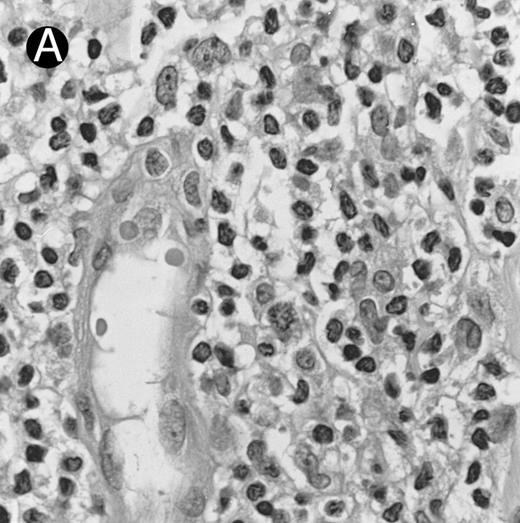

Lymph node biopsy of aggressive NK cell leukemia/lymphoma (case no. 37). There is a fairly monotonous, diffuse infiltrate of medium-sized cells with round nuclei. The neoplastic cells in this case resemble plasmacytoid monocytes.

There were very few to numerous granular lymphocytes in the peripheral blood. Some of the granular lymphocytes were indistinguishable from normal large granular lymphocytes, with round nuclei, dense chromatin, and pale cytoplasm with fine azurophilic granules (Fig 5A). Some granular lymphocytes had larger nuclei with more open chromatin and distinct nucleoli (Fig 5B); occasional nuclei could show indentations. The azurophilic granules were sometimes large and coarse. There were also circulating normoblasts and immature myeloid cells. Marrow involvement ranged from subtle to extensive. In histologic sections, irrespective of site, there was a monotonous infiltrate of medium-sized cells with round nuclei and fairly condensed chromatin (Fig 6). Karyorrhexis was prominent. The infiltrate was diffuse, interstitial, or angiocentric.

The immunophenotype as analyzed on fresh/frozen tissues was CD2+ CD3/Leu4− CD4− CD5− CD7− CD8− CD16− CD56+ CD57− (Fig 7). In paraffin sections, the neoplastic cells showed reactivity with the polyclonal CD3ε antibody. In all cases, nuclear labeling for EBER was observed in the majority of neoplastic cells.